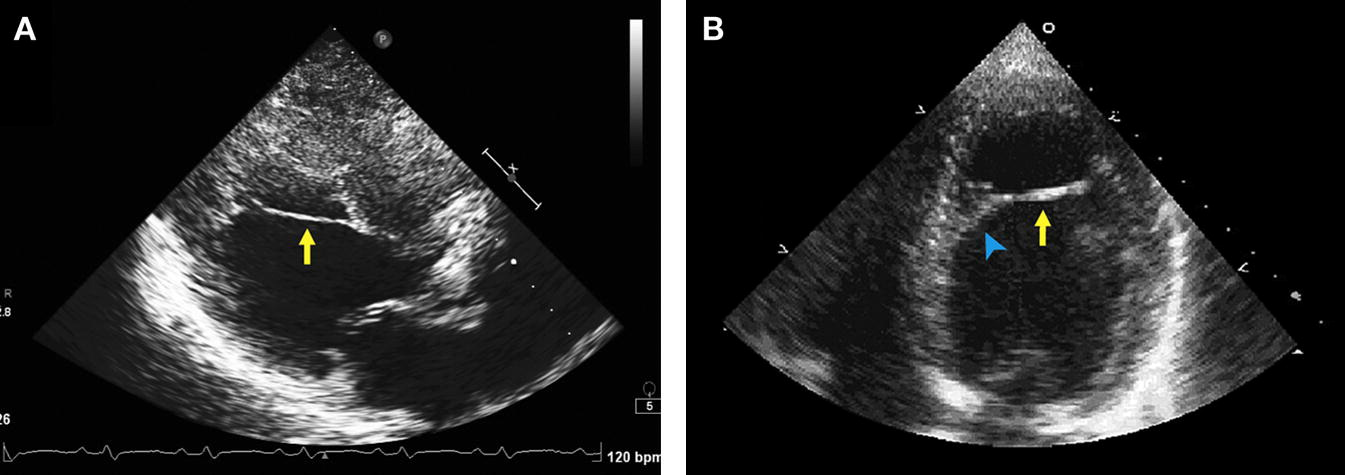

Apical HCM

• "Spade-like" LV cavity on diastole

• Can have apical wall motion abnormalities (hypokinesis and aneurysm formation)

• Early dx can be missed (giant negative t waves are a clue)

• Strain may demonstrate apical dyskinesia

• Mid-cavity obliteration and gradient may be present

Mimic

Apically Displaced Papillary Muscle